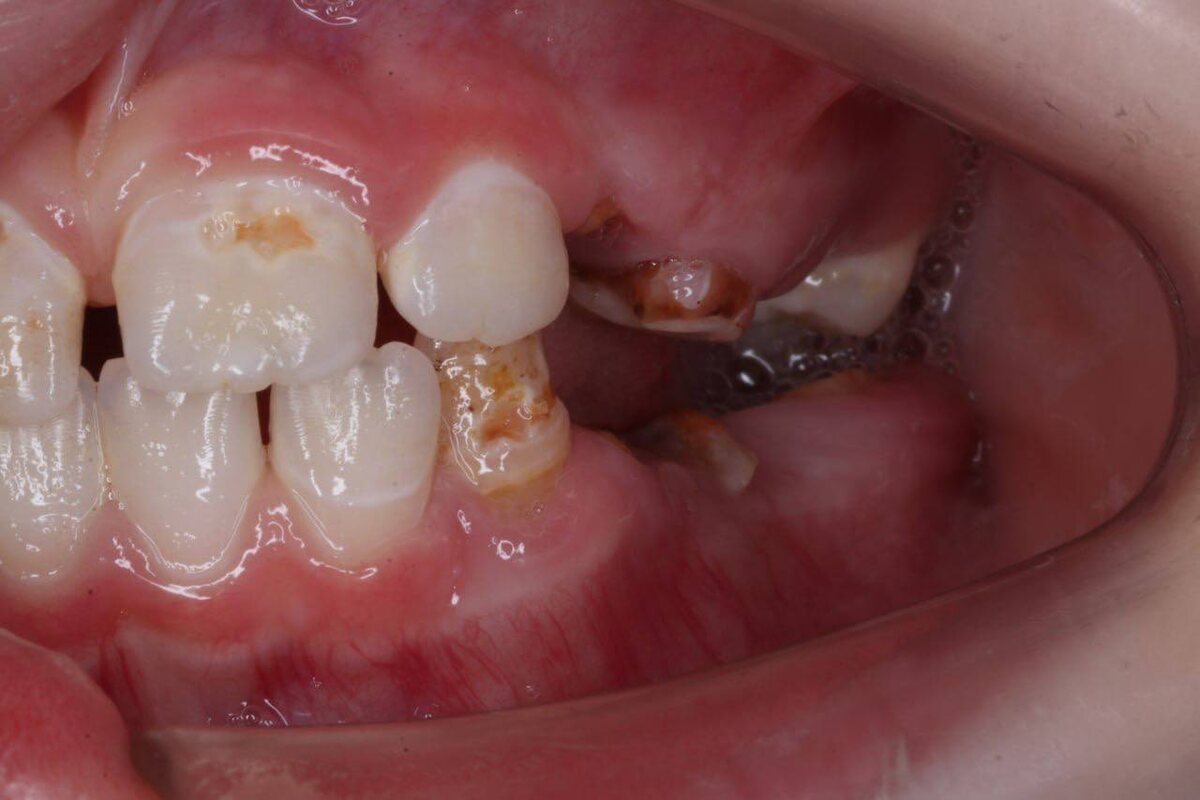

Девочка, 6 лет, негативный опыт, ранее — лечение в наркозе.

Более месяца болит щека слева, несколько клиник рекомендуют удаление 36 и 46 зуба, санация в условиях наркоза.